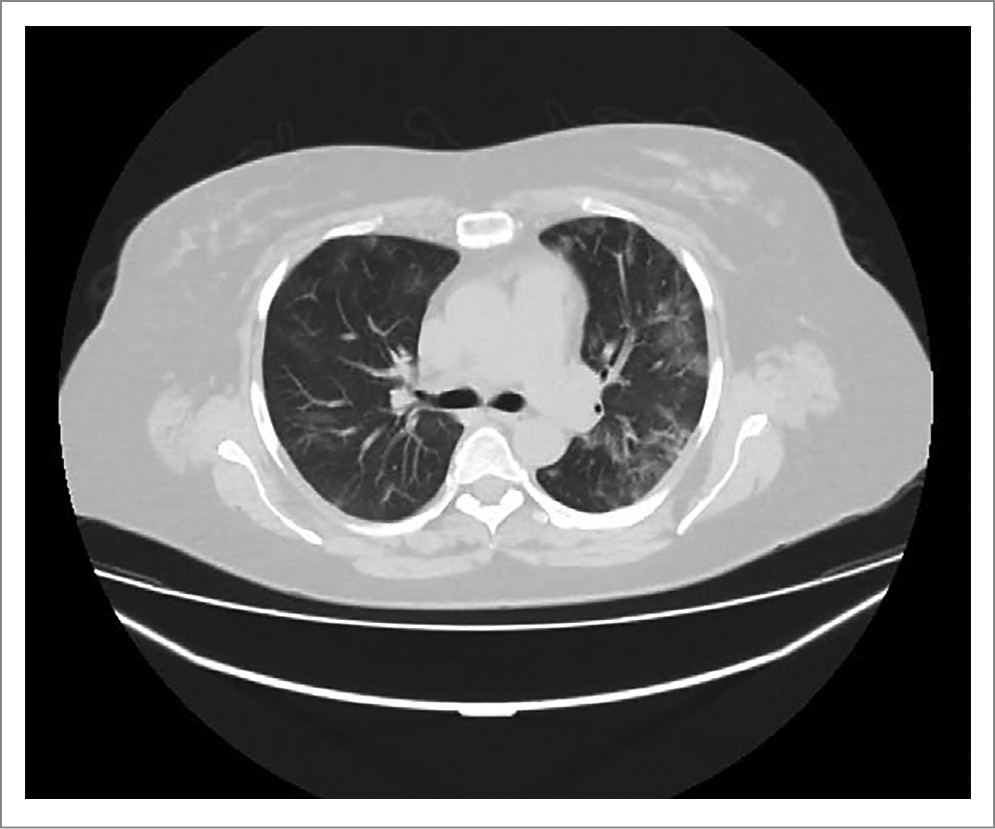

Выполнена мультиспиральная компьютерная томография (МСКТ) органов грудной клетки, выявлены немногочисленные двусторонние зоны уплотнения по типу «матового стекла» различной протяженности, преимущественно с периферическим распределением. Картина соответствовала 1-й степени тяжести согласно классификации по данным компьютерной томографии (КТ); рис. 1.

Рис. 1. Пациентка П. МСКТ органов грудной клетки (1-й день госпитализации).